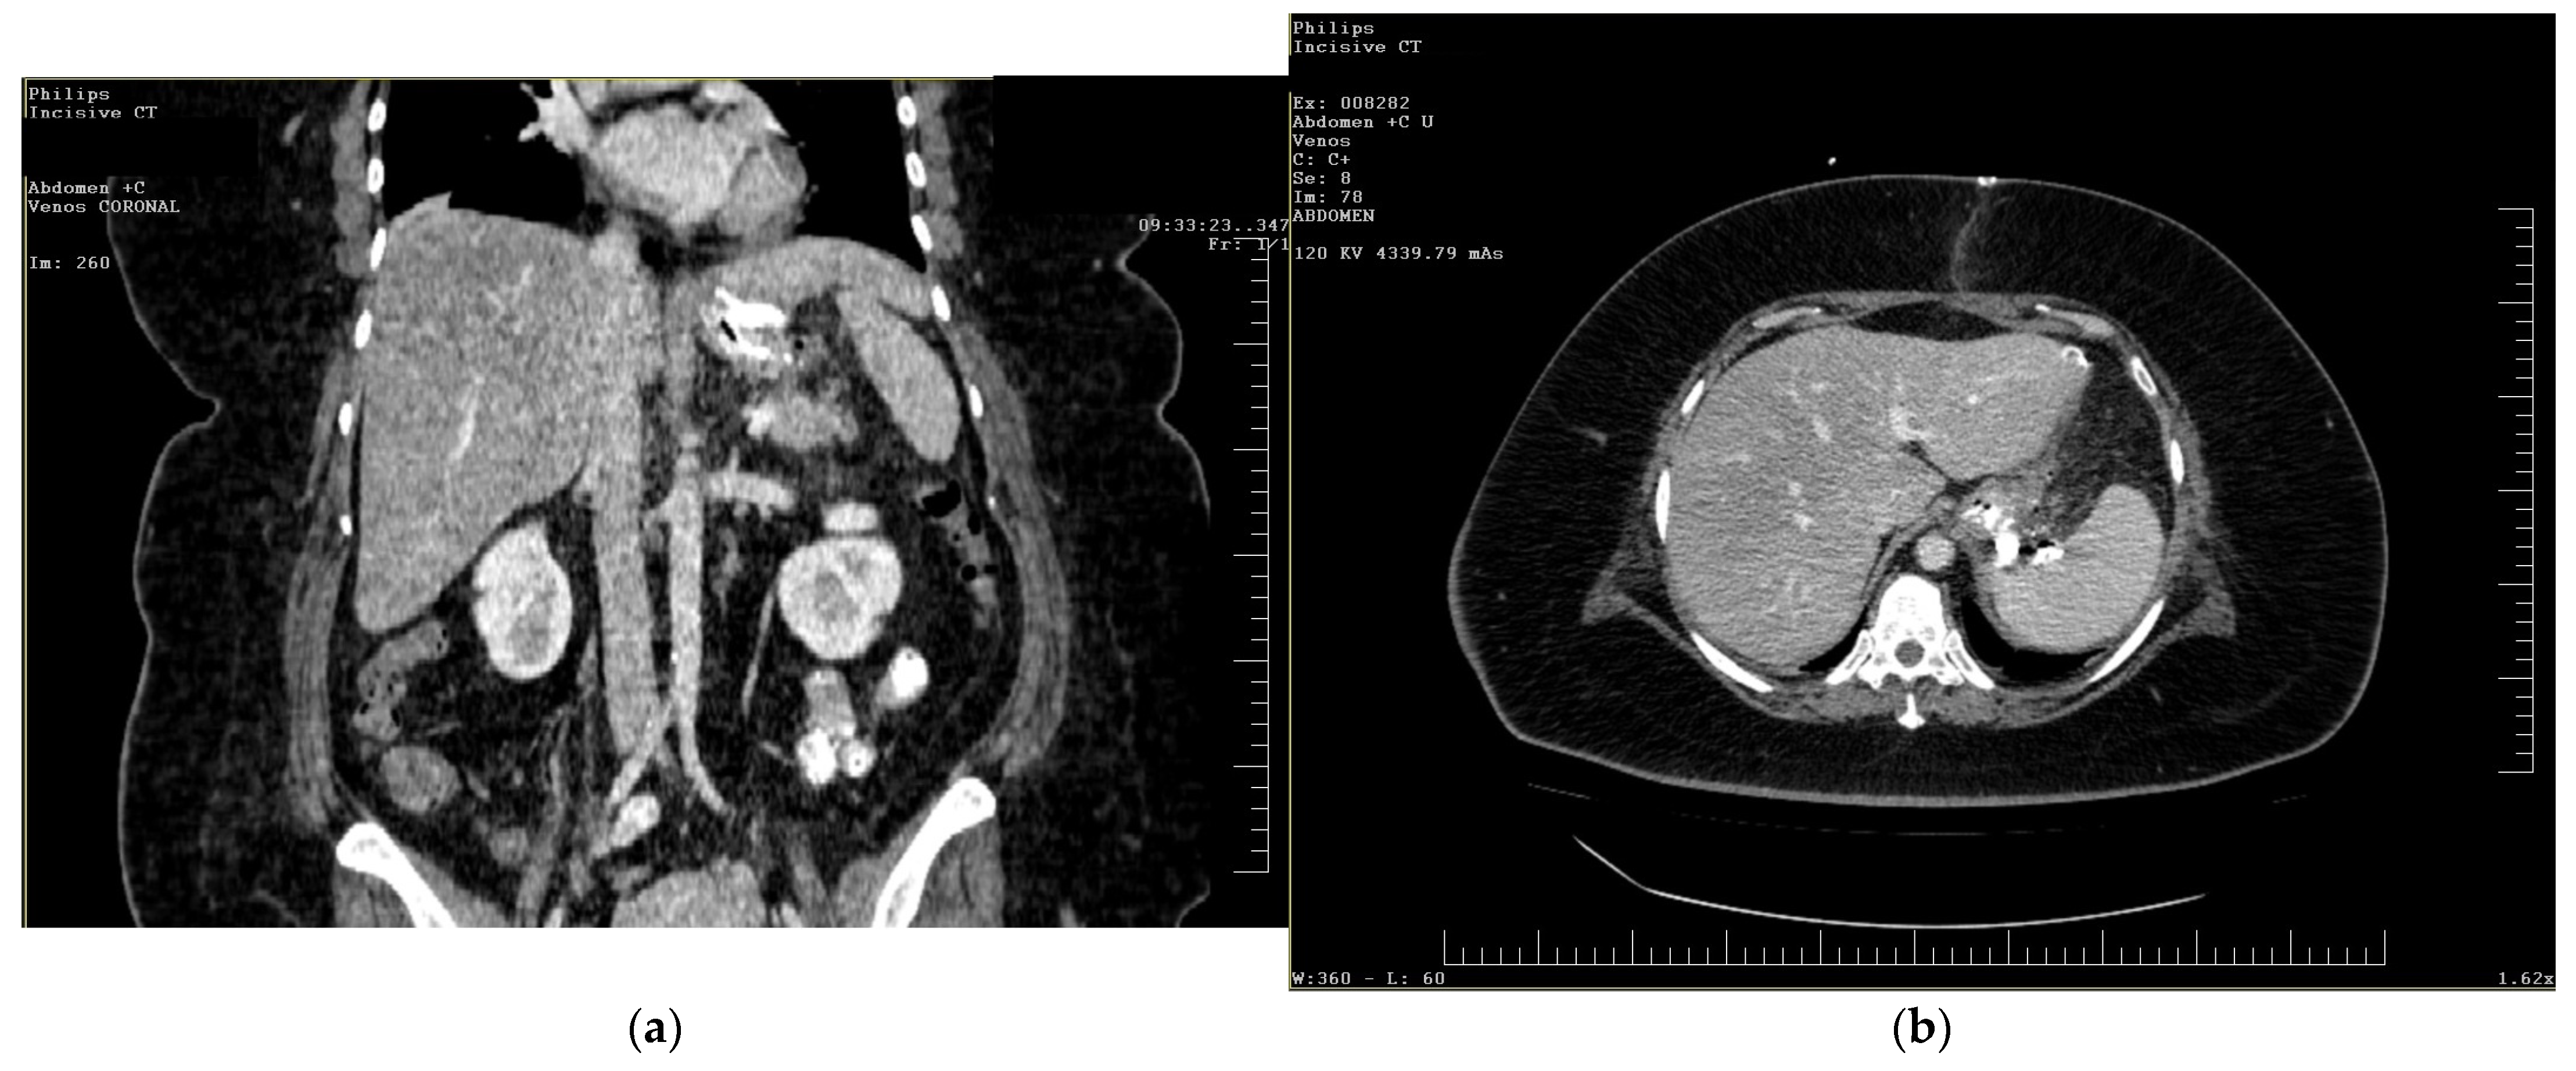

Follow-up staged procedures were performed at 6–7-day intervals, consisting of endoscopic replacement of the E-VAC system at the fistula site, with continuous monitoring of its evolution through direct endoscopic assessment. After six consecutive exchanges of the double-lumen endoluminal vacuum system, endoscopic evaluation confirmed complete closure of the fistulous tract, allowing the gradual reintroduction of oral intake (only liquid form). Under close supervision, the patient tolerated oral feeding for one week, with serial contrast studies using iopamidol confirming the absence of residual fistulous communication (Figure 3).

Figure 3. Contrast abdominal radiography—with E-VAC in place without leakage of the contrast substance.